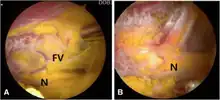

Surgery involves a nerve decompression with or without muscle resection.[5] The surgery can be performed with external incisions (open surgery) or endoscopically. Endoscopy allows for complete sciatic nerve visualization and access for decompression in the extrapelvic gluteal space.[1] The goal of surgery is to restore normal nerve kinematics and nerve conduction. During surgery this is measured by nerve conduction studies and electromyography, as well as observing the sciatic nerve mobility while the patients hips are moved.[1][2] This testing can be done before and after the decompression to verify improvement before concluding the surgery.